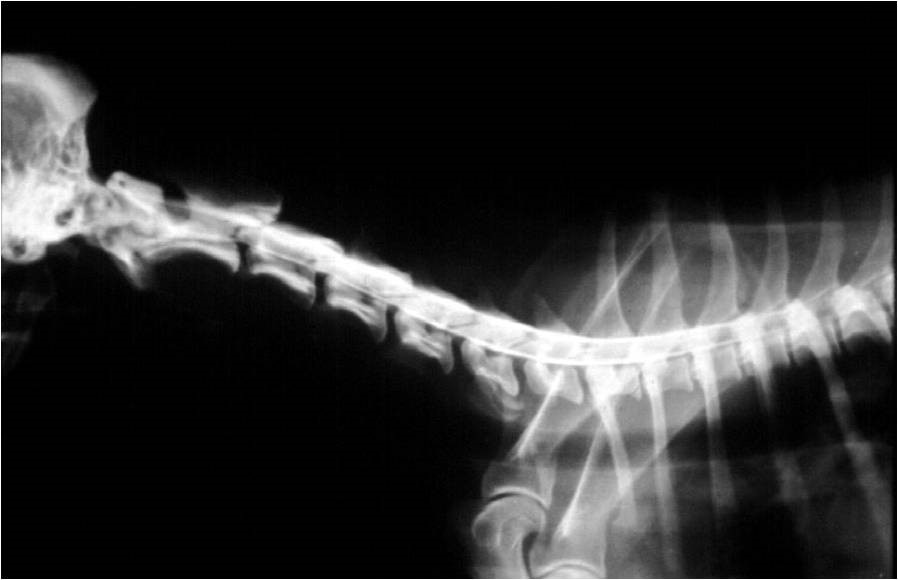

Nyaki myelogram